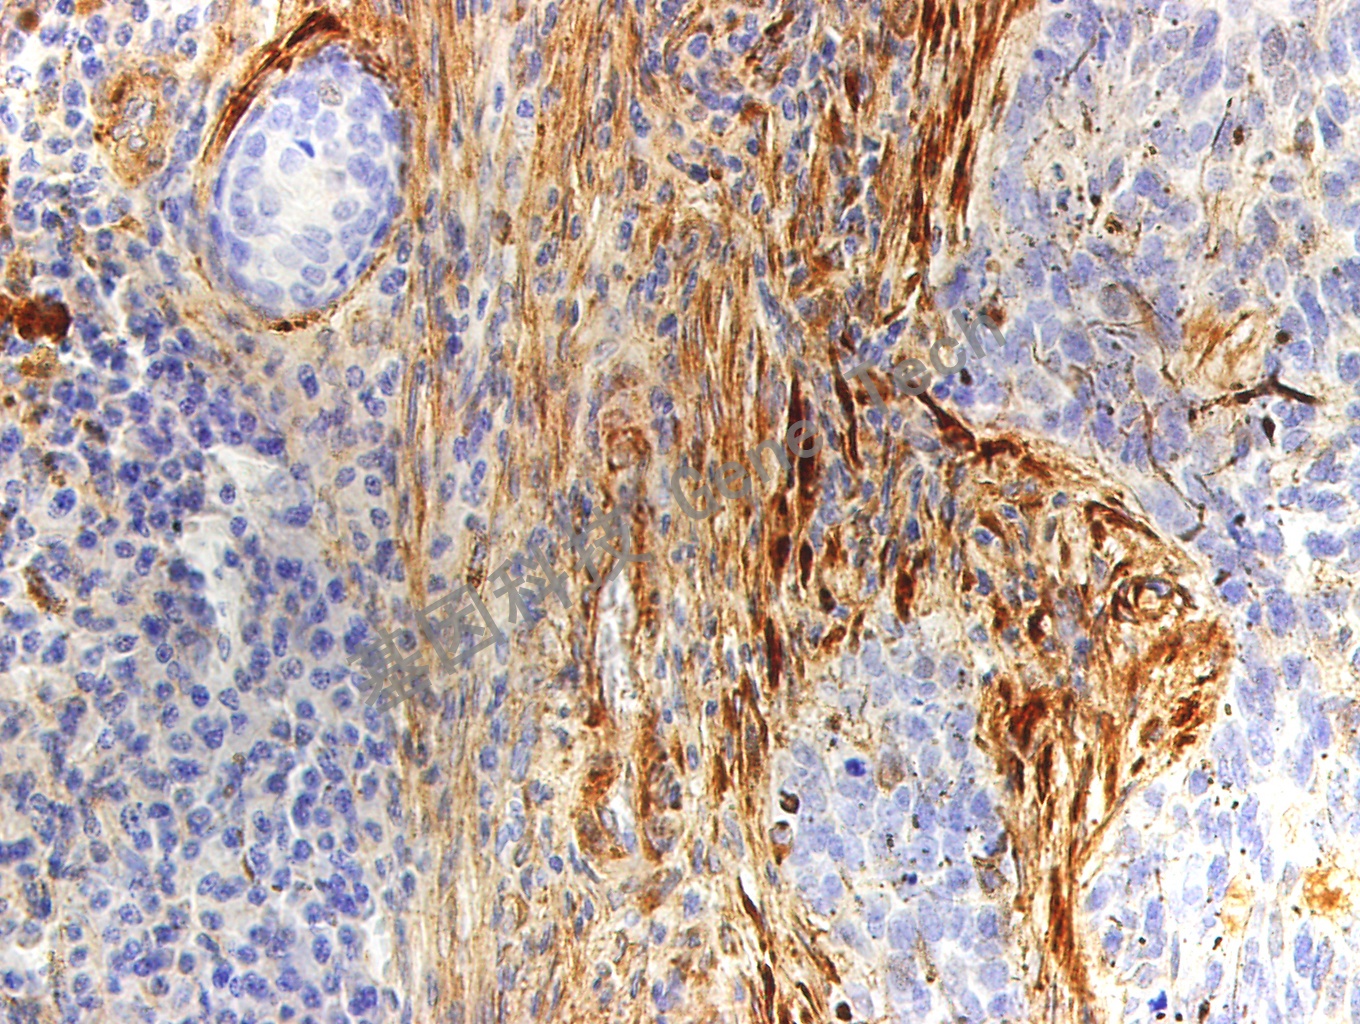

| 簡介:Fibronectin/FN(纖連蛋白)是細胞外基質的重要組分,參與細胞分化、遷移以及腫瘤浸潤等過程。此抗體用于輔助臨床對于多種惡性上皮腫瘤的浸潤和預后判斷。 | ||

| 皮膚石蠟切片,用 Fibronectin(GT2178)染色,細胞漿陽性,DAB 顯色。 | ||